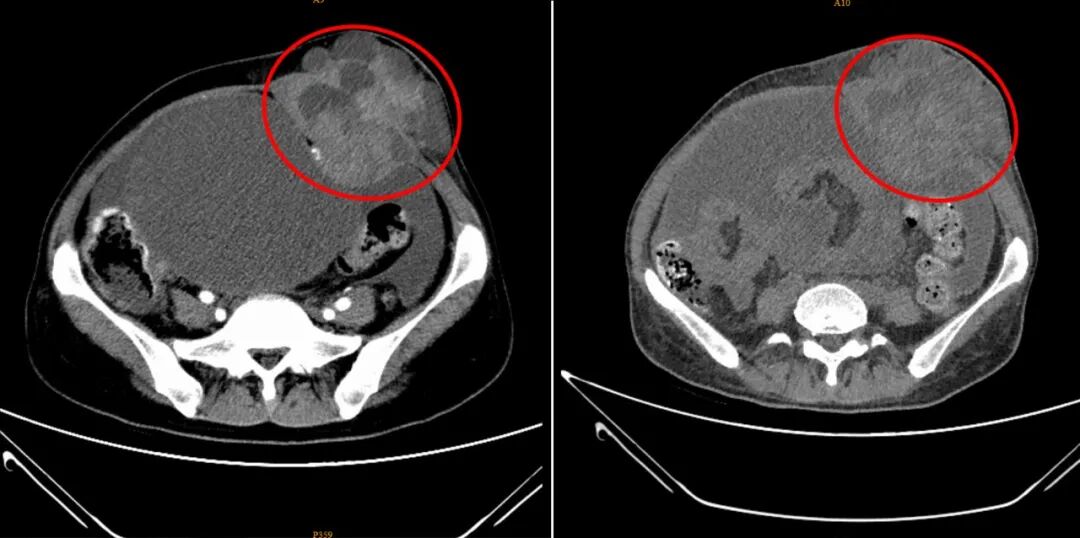

孙女士在深圳华侨医院治疗短短一个月的前后对比CT影像图。病灶部位呈现出体积显著缩小、边界趋于清晰、内部密度更加均匀的积极变化,表明治疗已取得明显成效。

在深圳华侨医院的精准微创治疗下,孙女士的身体状况发生了翻天覆地的变化,这份变化,不仅体现在检查报告上,更体现在她实实在在的身体感受中。接受冷冻消融术后不久,她就发现腹部的肿瘤肿块有了明显缩小,“用手摸能感觉到小些,从外观都能看出来,比之前拍片子的时候小了不少。” 而最让她欣喜的是,困扰她许久的睡眠问题彻底解决了,曾经两三个月彻夜难眠、只能趴着休息的她,如今能像正常人一样平躺、侧睡,“枕着一个枕头就能睡好觉,这种轻松的感觉太久没有了,我现在晚上睡觉特别香。”